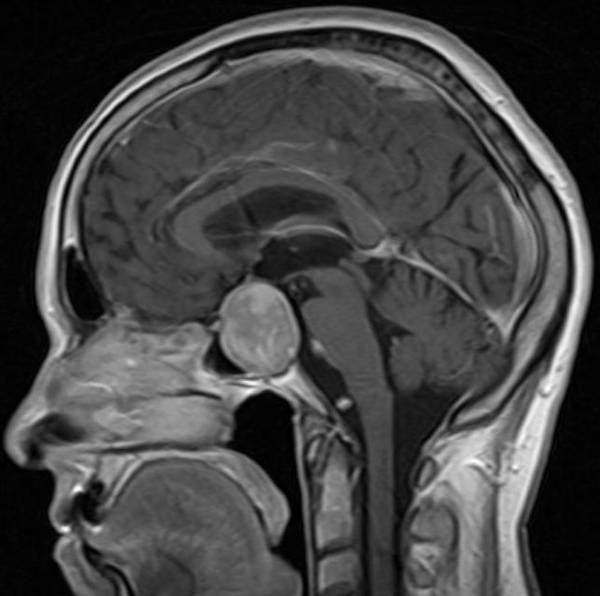

- Компьютерная томография;

- Магнитно-резонансная томография головного мозга.